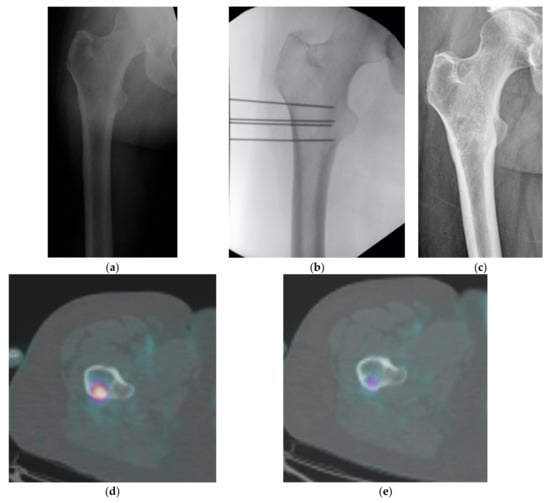

| GUIDANCE | |||||

| Intensifier | 22 | 58% | |||

| CT | 16 | 42% | |||